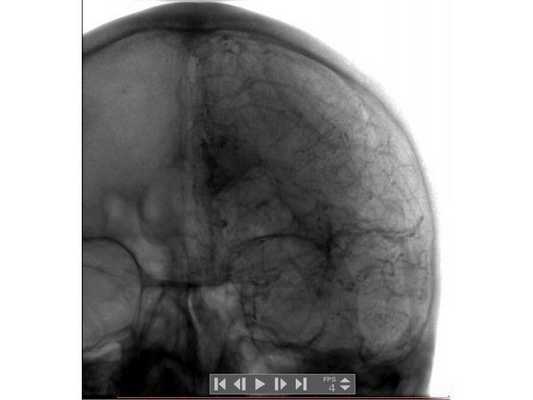

Анализ крови на алкоголь — 0 промилле. Выполнена диагностическая люмбальная пункция, выявлено субарахноидальное кровоизлияние: 10-15 эритроцитов в поле зрения. При помощи эхоэнцефалоскопии обнаружено смещение срединных структур головного мозга на 3-4 мм влево. Т.е. у пациента имеются клинические данные, указывающие на внутричерепную гематому справа, но при отсутствии КТ/МРТ-диагностики определить её объём и локализацию сложно. Для дальнейшего диагностического поиска пациенту выполнена церебральная ангиография. На ангиограммах отмечено отжатие сосудистой сети правого полушария головного мозга от костей свода черепа почти на 10 мм (рис. 1). В левом полушарии патологии не выявлено (рис. 2).

Данный клинический случай показывает, что при отсутствии КТ/МРТ ангиографическое исследование позволяет локализовать внутричерепную гематому и приблизительно оценить её объём. Источник гематомы верифицирован также благодаря этому виду обследования. Если почитать старые руководства по нейрохирургии 70-80-х годов прошлого века, можно убедиться, что церебральная ангиография очень часто применялась для диагностики гематом головного мозга, опухолей, не говоря уже о сосудистой патологии.